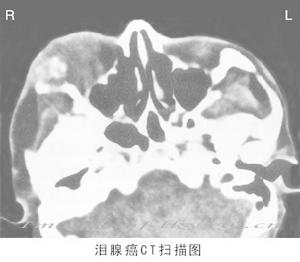

3. CT掃描 腫瘤呈圓形、類圓形或橢圓形,邊界清,光滑,位於淚腺窩,呈軟組織密度,均質,(圖)。少數有液化腔可呈片狀低密度區。淚腺窩骨質因長期壓迫可吸收變薄,甚至骨缺失。

| 軸位CT顯示左眶淚腺多形性腺瘤,腫瘤位於淚腺窩,圓形,邊界清,密度均勻。 |

淚腺多形性腺瘤 |